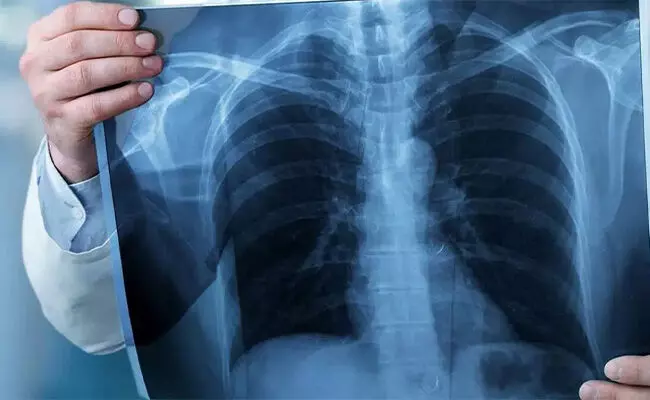

ಇಂದು ನವೆಂಬರ್ 8 ವಿಶ್ವ ರೇಡಿಯೊಗ್ರಫಿ ದಿನಾಚರಣೆ. ಆದಿವ್ಯಾಧಿಗಳು ಮಾನವರ ಜೀವನದುದ್ದಕ್ಕೂ ಜಗತ್ತಿನ ಜನತೆಯನ್ನು ಕಾಡುತ್ತಲೇ ಇರುತ್ತವೆ. ವೈದ್ಯರ ಸಲಹೆ, ಚಿಕಿತ್ಸೆಯಿಂದ ರೋಗ ಬವಣೆಗಳು ಪರಿಹರಿಸಲ್ಪಡುತ್ತಿದ್ದರೂ ಕೆಲವೊಮ್ಮೆ ಮಾನವ ಶರೀರದ ಒಳಗಿನ ಸ್ಥಿತಿಯನ್ನು ತಿಳಿಯಲು ತಂತ್ರಜ್ಞಾನಗಳು ಅವಶ್ಯಕ. ರೋಗ ಮೂಲವನ್ನು ಹುಡುಕುವ ಸಲುವಾಗಿ 1895ರ ನವೆಂಬರ್ 8ರಂದು ಜರ್ಮನಿಯ ಮೆಕ್ಯಾನಿಕಲ್ ಇಂಜಿನಿಯರ್ ಹಾಗೂ ಭೌತಶಾಸ್ತ್ರ ಪರಿಣಿತ ವಿಜ್ಞಾನಿ ವಿಲ್ಹೆಲ್ಮ್ ಕಾನ್ರಾಡ್ ರಾಂಟ್ಜೆನ್ ಅವರು ವಿಕಿರಣ ತಂತ್ರಜ್ಞಾನ ಆವಿಷ್ಕರಿಸಿ ಯಶಸ್ವಿಯಾದರು.

ರಾಂಟ್ಜೆನ್ ಅವರ ಸಂಶೋಧನೆಯಿಂದ ಪ್ರಪಂಚದುದ್ದಕ್ಕೂ ರೋಗಿಗಳ ಶರೀರದ ಒಳಗಿನ ಸಮಸ್ಯೆಯನ್ನು ವಿಕಿರಣ ಅಥವಾ ರೇಡಿಯೊಗ್ರಫಿಯ ಮೂಲಕ ತಿಳಿಯಲು ಆ ಕಾಲದಲ್ಲಿ ತಂತ್ರಜ್ಞಾನ ಬಳಕೆಯಾಯಿತು.

ರಾಂಟ್ಜೆನ್ ಅವರು ಕಂಡು ಹಿಡಿದ ವಿಕಿರಣ ಪರೀಕ್ಷೆ ಎಕ್ಸ್ ರೇ ಎಂದು ಪ್ರಸಿದ್ಧಿಯಾಯಿತು. 1901ರಲ್ಲಿ ರಾಂಟ್ಜೆನ್ ಅವರ ಈ ವೈಜ್ಞಾನಿಕ ಸಾಧನೆಗೆ ನೊಬೆಲ್ ಪುರಸ್ಕಾರ ನೀಡಿ ಗೌರವಿಸಲಾಗಿದೆ.

ಆರೋಗ್ಯ ರಕ್ಷಣೆ ಮತ್ತು ಜಾಗೃತಿಯಲ್ಲಿ ಸಹಕರಿಸುವ ರೇಡಿಯೊಗ್ರಫಿ ಅಥವಾ ವಿಕಿರಣ ಶಾಸ್ತ್ರ ಜನೋಪಯೋಗಿಯಾದ ಜಾಗತಿಕ ತಂತ್ರಜ್ಞಾನ. ಈ ವರ್ಷದ ರೇಡಿಯೊಗ್ರಫಿ ದಿನದ ಧ್ಯೇಯದಂತೆ ಕಾಣದ ವಿಷಯವನ್ನು ಹುಡುಕುವ ಅಥವಾ ಕಾಣುವ ರೇಡಿಯೊಗ್ರಾಫರ್ ಎಂಬಂತೆ ವಿಕಿರಣ ಶಾಸ್ತ್ರದ ಸಹಾಯದಿಂದ ಸಂಕೀರ್ಣ ಆರೋಗ್ಯ ಸಮಸ್ಯೆಗಳನ್ನು ನಿಯಂತ್ರಿಸಲು ಸಹಾಯವಾಗಬಹುದು.

ರೇಡಿಯಾಲಜಿ ಮತ್ತು ರೇಡಿಯೊಗ್ರಫಿ ವಿಜ್ಞಾನವು ಕೆಲವಾರು ಸಂದರ್ಭಗಳಲ್ಲಿ ಚಿಕಿತ್ಸೆ ನೀಡುವ ವೈದ್ಯರಿಗೆ ರೋಗ ಪತ್ತೆಗೆ ನೆರವು ನೀಡುತ್ತದೆ.